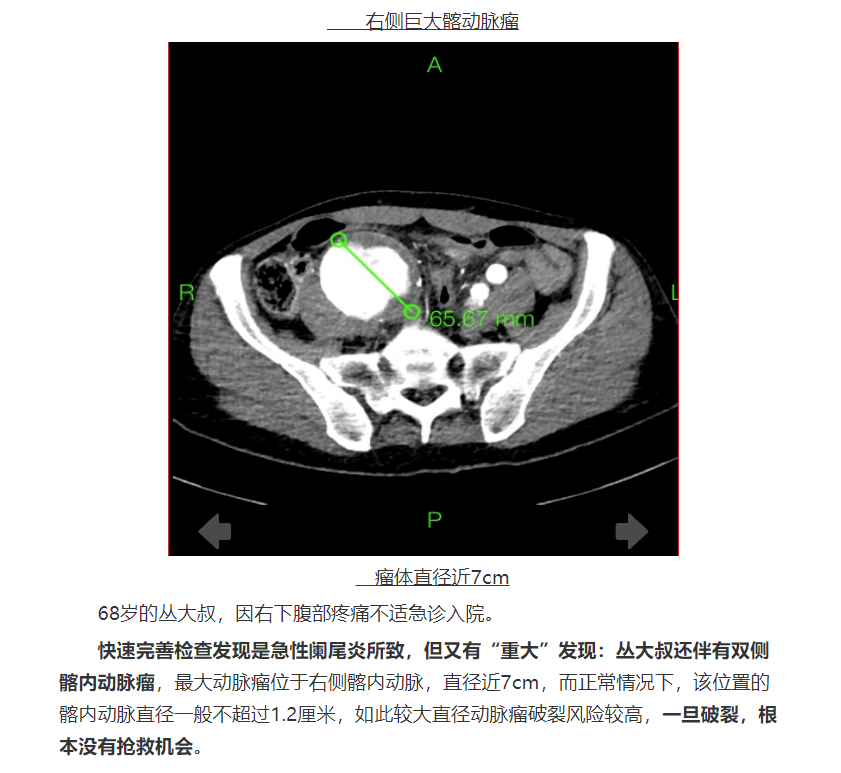

相信内容:https://app.binzhouw.com/sy/cms_template/100/000/389/index.shtml?appId=e933fd08-a0fd-4ce1-9a03-a1ba044bc604&jsonUrl=https://app.binzhouw.com/sy/cms_mob/v200/cms_news/000/000/030/505/000000030505082_29a8ed2f.json&resourcesUrl=https://app.binzhouw.com/cms_mob/v200/cms_oth/chan.json&jy_uid=200002986&newsId=030505082